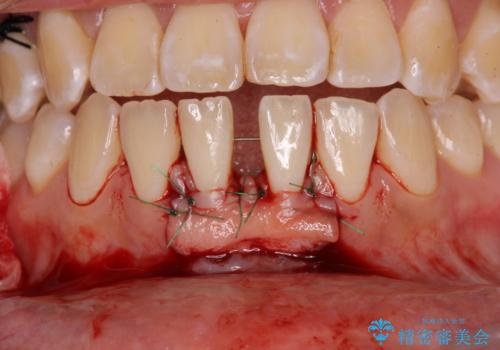

舌のトレーニングをしっかりと行っていくことを前提に、歯肉移植による根面被覆と、部分矯正によるすきっ歯の改善を行うこととしました。

歯肉移植と矯正治療後には非常に満足のいく仕上がりとなりましたが、舌の突出癖は残存しており、今後歯肉退縮とすきっ歯になるリスクを抱えた状態での治療終了となりました。

- 外科手術のため、術後に痛みや腫れ、違和感を伴います

- 歯周組織再生治療は患者様の状態によって術後の経過が異なります(見た目が改善しない場合もあります)